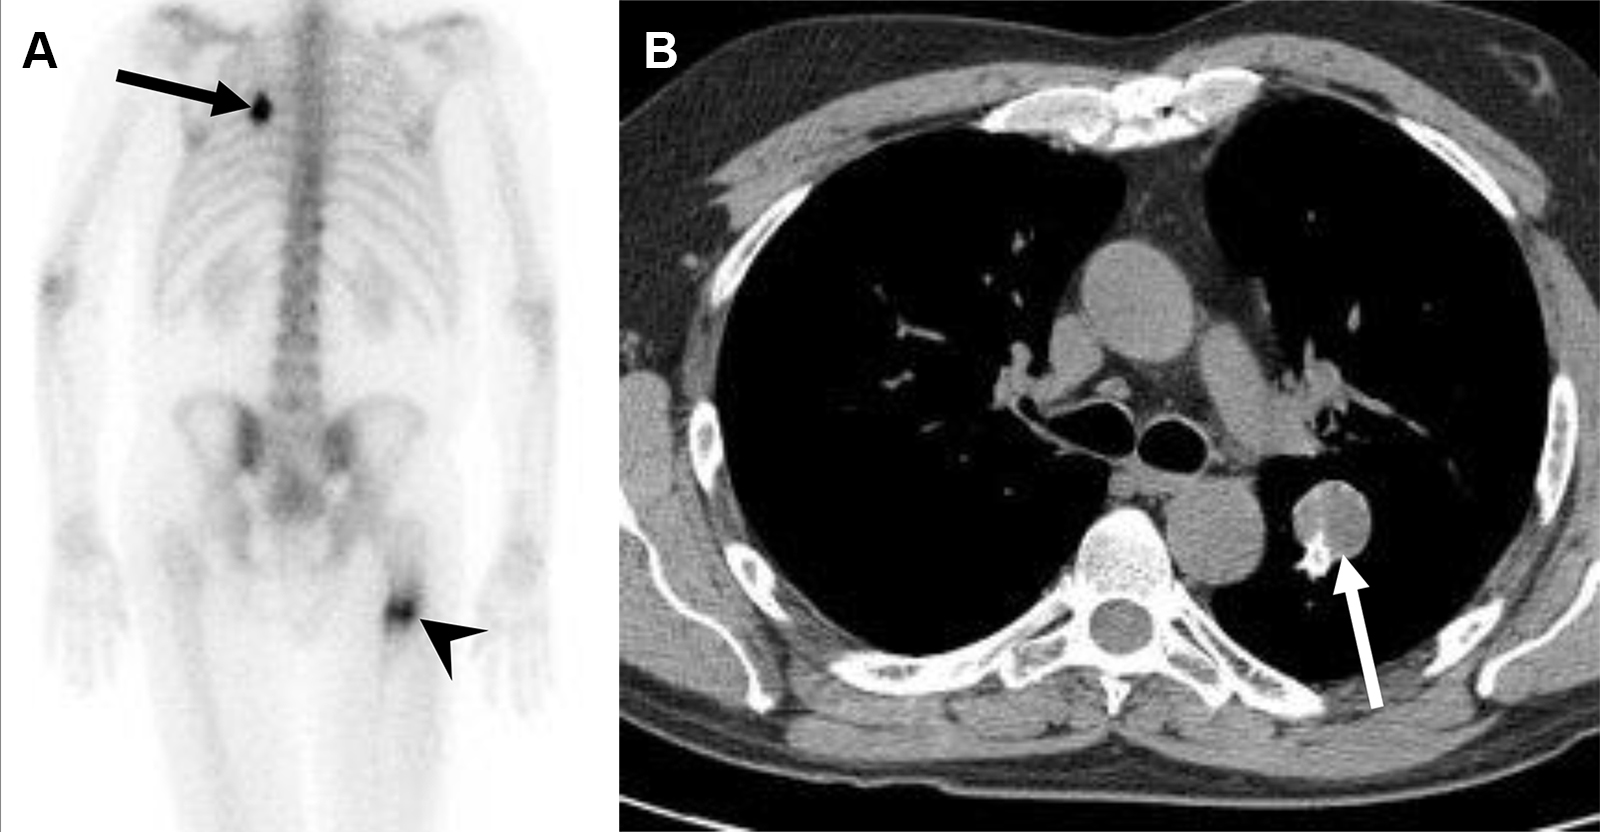

Metastasi costali e pleuriche con versamento pleurico in una donna di 63 anni con tumore al seno.

La scintigrafia ossea con 99mTc-MDP evidenzia una lieve ipercaptazione diffusa che ricalca l’emitorace destro, causata verosimilmente dall’accumulo di tracciante nel liquido pleurico maligno. È inoltre visibile una captazione longitudinale a carico dell’arco posteriore dell’XI costa destra. La TC conferma la natura della captazione, evidenziando il versamento pleurico, un ispessimento pleurico e le iniziali alterazioni osteosclerotiche a carico della costa interessata. Il caso dimostra come la scintigrafia ossea possa rilevare non solo le localizzazioni secondarie scheletriche dirette, ma anche segni indiretti di patologia extra-ossea adiacente (come la captazione pleurica).